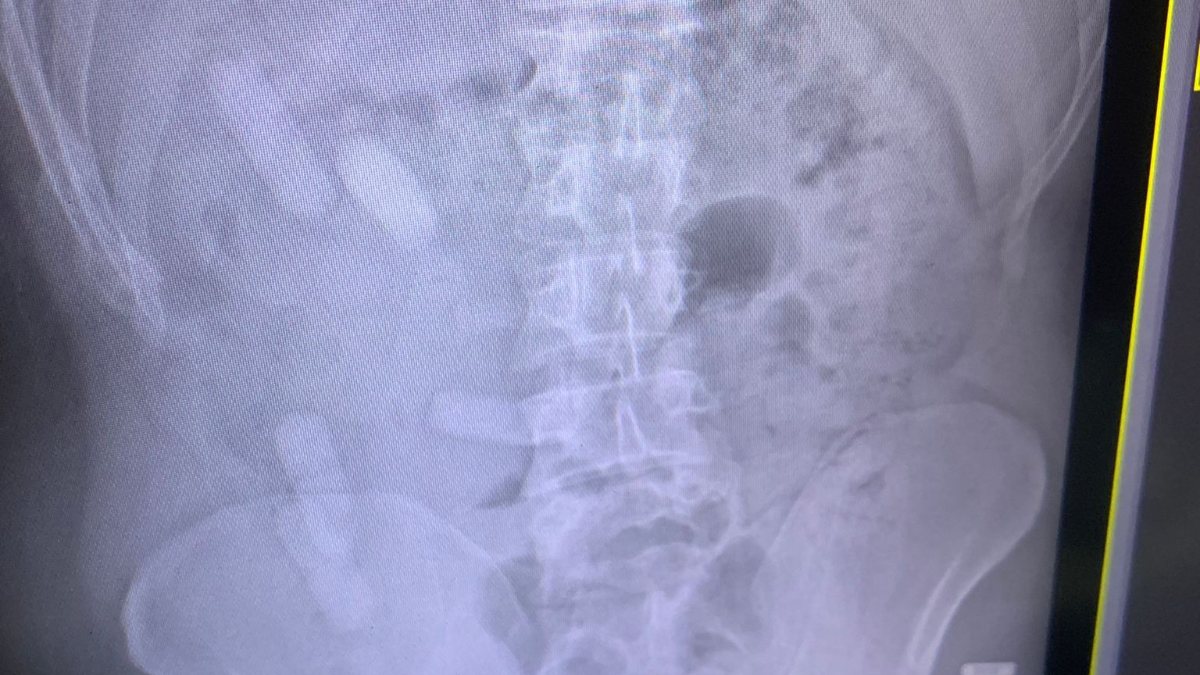

Şüphe ile A.E. isimli İranlı şahsa çekilen röntgen filminde, midesinde de 15 kapsül olduğu anlaşıldı.